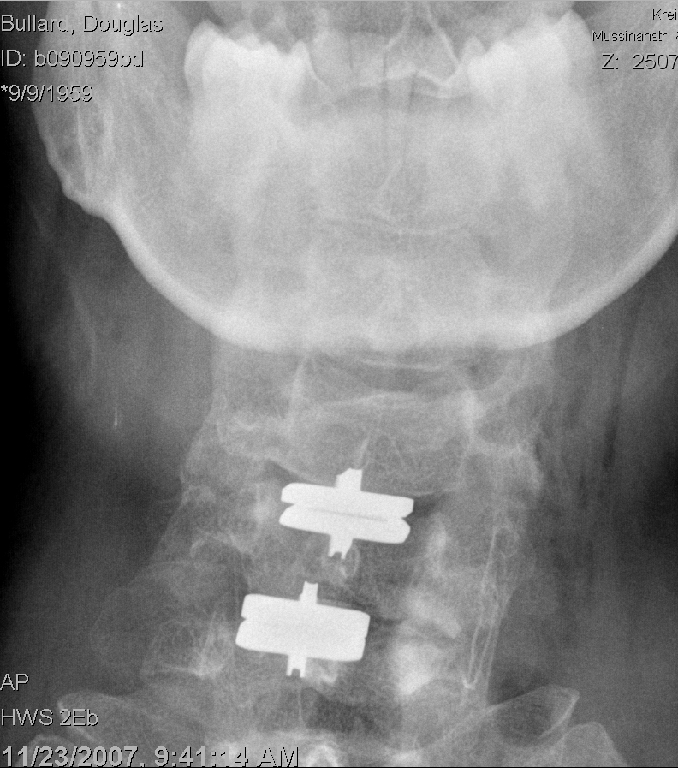

What all the fuss was about - my MRI. Notice that the spinal cord (the grey thing surrounded by white fluid) is pinched in two locations. Furthermore, there are white streaks in the spinal cord itself - that's it's way of going "ouch!", and those areas are damaged (myleopathy - literally, "death of nerves"). This is very bad, and if it continued, could have left me paralyzed.